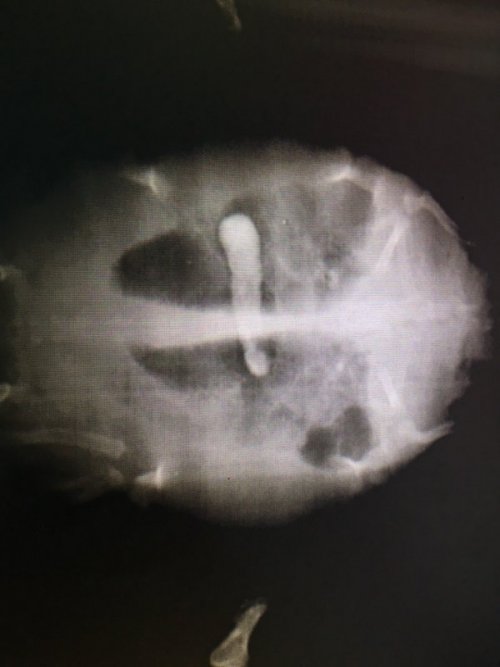

@moth Последний рентген делали в четверг. В пятницу были у герпетолога в Воронеже, сказала что на закупорку это не похоже ( на рентгене вроде как она по другому выглядит сказала ) . С кишечником и ногами последствия перенесенной пневмонии и общего слабого состояния. Глаза так сильно от авитаминоза заплыли, поэтому софрадекс нам не дал ни какого результата.  В общем из лечения , она сказала что сейчас нужно помогать черепахе набираться сил и лечить авитаминоз . Кормление принудительное через зонд  ( размягченный корм или даже рыбу нежирную отварную перемолотую с буленом ) . Сама на кануне пробовала корм размягчить и дать шприцом , но он все выплюнул. Воду повысить темпертуру, но она у нас и так на максимуме термометра  стоит. Курс витаминов Элевоит 0,1  1р в 7д (курс 3-4 инъекции) и катозал 0,1  1р в 3 дня ( 3-4 инъекции). На приеме в пятницу она уже сразу два укола нам сделала. Пока черепаха в таком же состоянии. Глаза отекшие , малоактивен. СКазали после первых уколов на 4-5 день уже должны наблюдаться изменения .

"Это мелкий, но уже половозрелый самец. Корм, который вы давали (мотыль, рыбное филе, Тортилла) практически не содержит кальция и жирорастворимых витаминов. При этом развивается отек век и прекращается кишечная перистальтика. Если у входа в тазовый канал скапливается кал или инородный материал, развивается обратимый парез задних конечностей. Если черепаха при этом грызла минеральный блок, то скорее всего, в кишке скопилась подкормка и вызвала частичную непроходимость. На первом снимке этот материал стоит в двенадцатиперстной кишке, на втором - продвинулся в подвздошную кишку, но еще не прошел в ободочную. Никакой пневмонии у черепахи не было, и байтрил вы кололи зря. На первом снимке на легочное поле справа проецируется петля кишки, вызывая затемнение, которое врач посчитал пневмонией. Поскольку вы не пишете, какой вес у черепахи, я не могу проверить, правильные ли дозы препаратов вам назначили. Нужно вводить ей в пищевод 2 мл/кг вазелинового масла, примерно раз в 5-6 дней. Проколоть нормальный курс борглюконата кальция, по 0,2 мл/100 г массы тела, через день, курс 10 уколов под кожу бедра. Элеовит уколоть дважды, с интервалом 2 недели, по 0,5 мл/кг. Катозал не нужен. Проблема с глазами закончится через неделю-две после того, как она прокакается. Тогда же заработают задние конечности. А вот проблемы с кальцием исчезнут только месяца через 2. Если черепаха снова начнет есть, переводите ее на гранулы Рептомин Энерджи или Бэйби. И другой корм вообще не давайте месяца 3-4, иначе в тот же день он перестанет есть гранулы.